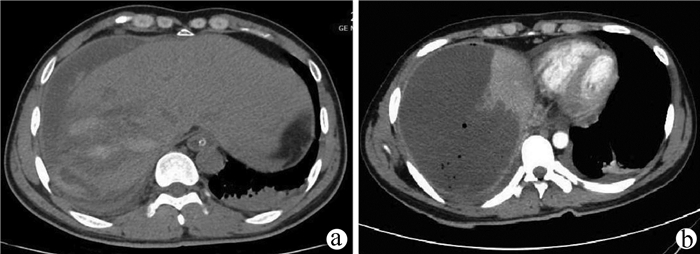

A case of huge intrahepatic biliary papillomatosis

Ziyue WANG, Daqun LIU, Jiaao YU, Jingxuan ZHANG, Guoyue LYU

2021, 37(11): 2651-2652. DOI: 10.3969/j.issn.1001-5256.2021.11.034

Abstract(810) HTML (178) PDF (2663KB)(51)

Abstract: